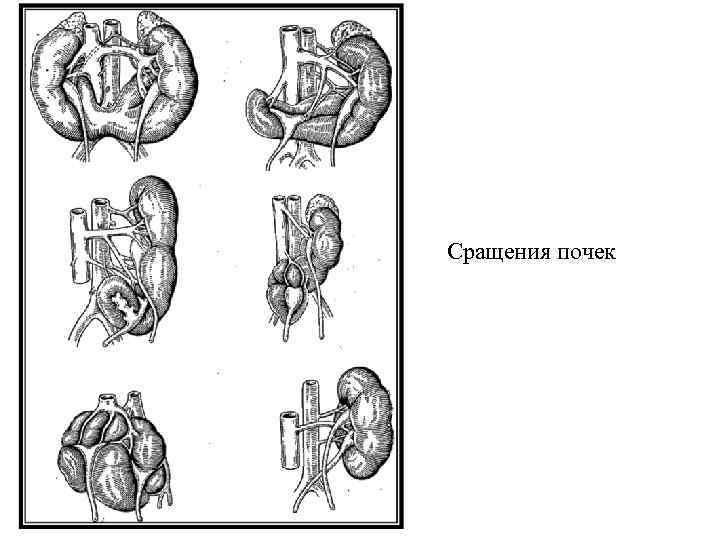

Аномалии расположения и формы почек Дистопия почек: односторонняя (грудная, поясничная, подвздошная, тазовая); перекрестная. Сращение почек: одностороннее (L-образная почка); двустороннее (подковообразная, галетообразная, асимметричные - L- и Sобразные почки).

Аномалии расположения и формы почек Дистопия почек: односторонняя (грудная, поясничная, подвздошная, тазовая); перекрестная. Сращение почек: одностороннее (L-образная почка); двустороннее (подковообразная, галетообразная, асимметричные - L- и Sобразные почки).

Сращения почек

Сращения почек